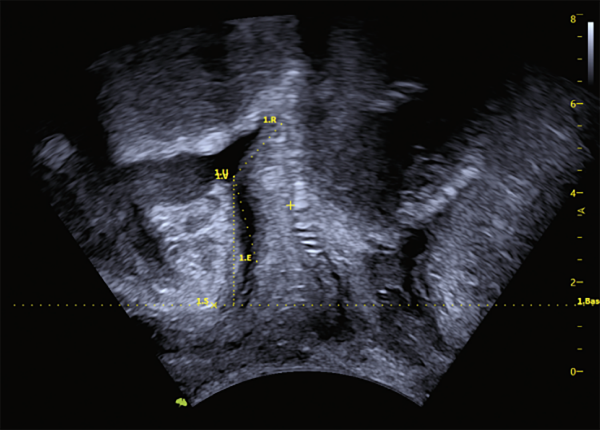

VINNO Technology introduce una nueva tecnología que utiliza inteligencia artificial (IA) para la medición pélvica, VAim Levator Ani y VAim Ant. Pelvic, ésta proporciona resultados de medición pélvica con un solo toque. Permite evaluar la estructura pélvica posparto de una manera fácil y precisa.

Los ecógrafos VINNO cuentan con esta tecnología, esto le proporcionará una ventaja estratégica a su clínica u hospital.

Realizará estudios, que normalmente requieren mucho tiempo, en un instante.